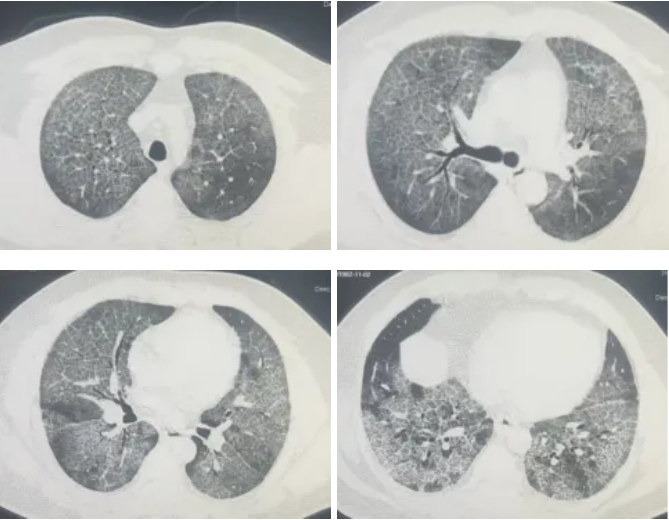

QQ截图20260326083313

▲ 灌洗前胸部CT

接诊后,呼吸与危重症医学科冯永海团队对孟师傅的胸部CT进行了细致分析,发现双肺弥漫性改变,高度怀疑肺泡蛋白沉积症。